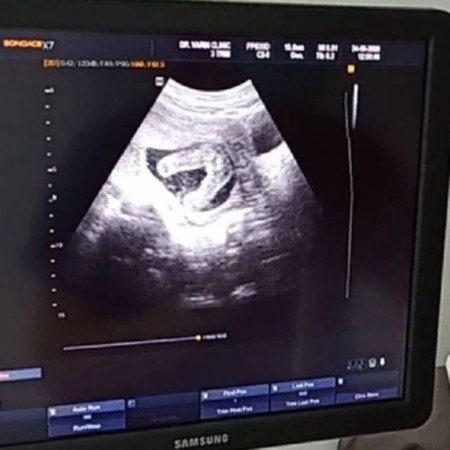

ภาพอัลตร้าซาวด์น้อง 17w3d คุณหมอยังไม่คอนเฟิร์มว่าเป็นผู้หญิง100% จากประสบการณ์แม่ๆ คิดว่าน้องเป็น ผญ หรือ ผช คะ

ภาพซาวเหมือนกันเลยค่ะ แถมหมอยังพูดเหมือนกันว่าไม่คอนเฟิมว่าเป็น ผญ. 100%

รอซาวด์อีกทีตอน 20 wขึ้นไปค่ะ เพราะอวัยวะเพศจะพัฒนาจนสมบูรณ์แล้ว

เรียบๆ ไม่มีอะไรยื่นออกมาแบบนี้ผู้หญิงค่ะ

น่าจะ ญ นะคะ ไม่มีอะไรโผล่ออกมา